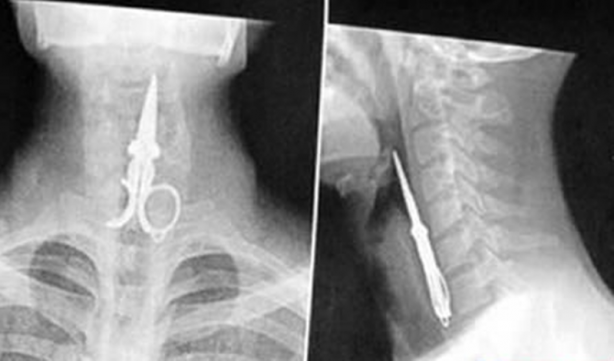

Makas yutan bir adam.

#8